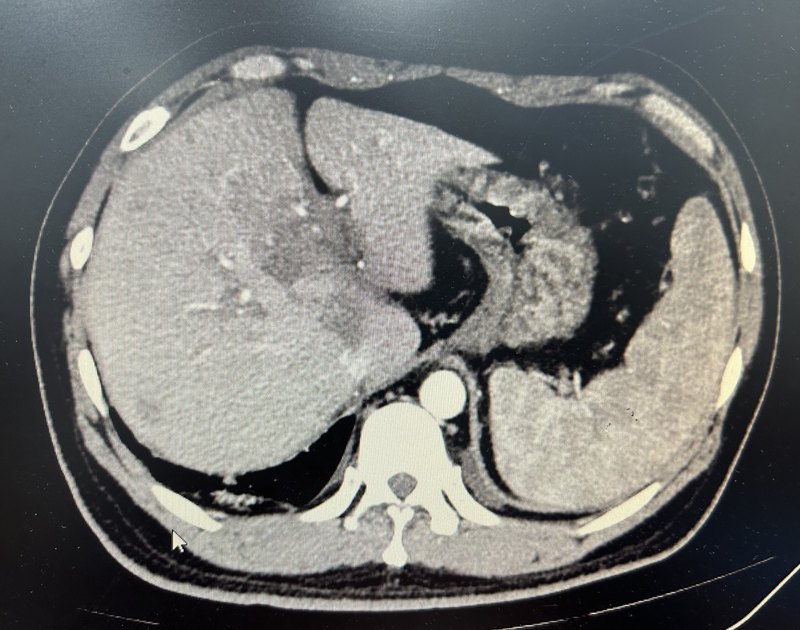

脾動(dòng)脈主干栓塞聯(lián)合脾微波消融治療巨脾并門脈血栓案例分享

患者青年男性乙肝肝硬化重度脾亢門脈高壓套扎治療期間出現(xiàn)門脈血栓。行脾動(dòng)脈主干栓塞后抗凝治療及脾微波消融治療。治療后門脈血栓明顯減少,繼續(xù)抗凝治療。治療前巨脾并門脈血栓。脾動(dòng)脈主干栓塞后行脾微波消融及利伐沙班抗凝治療。脾門高密度為脾動(dòng)脈主干彈簧圈。脾微波消融治療后脾臟可見大片壞死。治療后門脈血栓明顯減少。點(diǎn)評(píng):巨脾重度脾亢門脈高壓并門脈血栓是臨床比較難處理的情況,因?yàn)殚T脈高壓及重度脾亢會(huì)限制我們抗凝和溶栓治療的使用。但是如果不積極干預(yù),門脈血栓會(huì)逐漸進(jìn)展導(dǎo)致難以逆轉(zhuǎn)并發(fā)癥發(fā)生。我們采取先脾動(dòng)脈主干彈簧圈栓塞降低門脈壓力提高抗凝治療的安全性后,給予小劑量抗凝治療,同時(shí)通過脾消融進(jìn)一步糾正脾亢,慢慢達(dá)到既降低門脈壓力和糾正脾亢又逐漸消除門脈血栓的目的。這個(gè)方案還可以糾正脾動(dòng)脈盜血從而改善肝功能,值得臨床進(jìn)一步嘗試和驗(yàn)證。